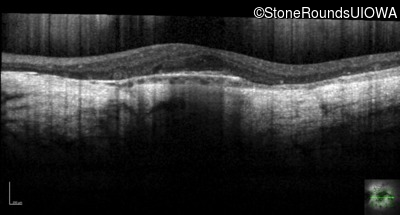

Optical Coherence Tomography - Right - 5/300

Exemplar / OCT Stack

OCT Stack